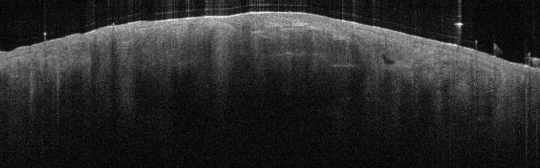

VA33: Superior Nasal Ala, Basal Cell Carcinoma, Nodular

- * indicate areas of necrotic cells not yet undergone liquifactive necrosis